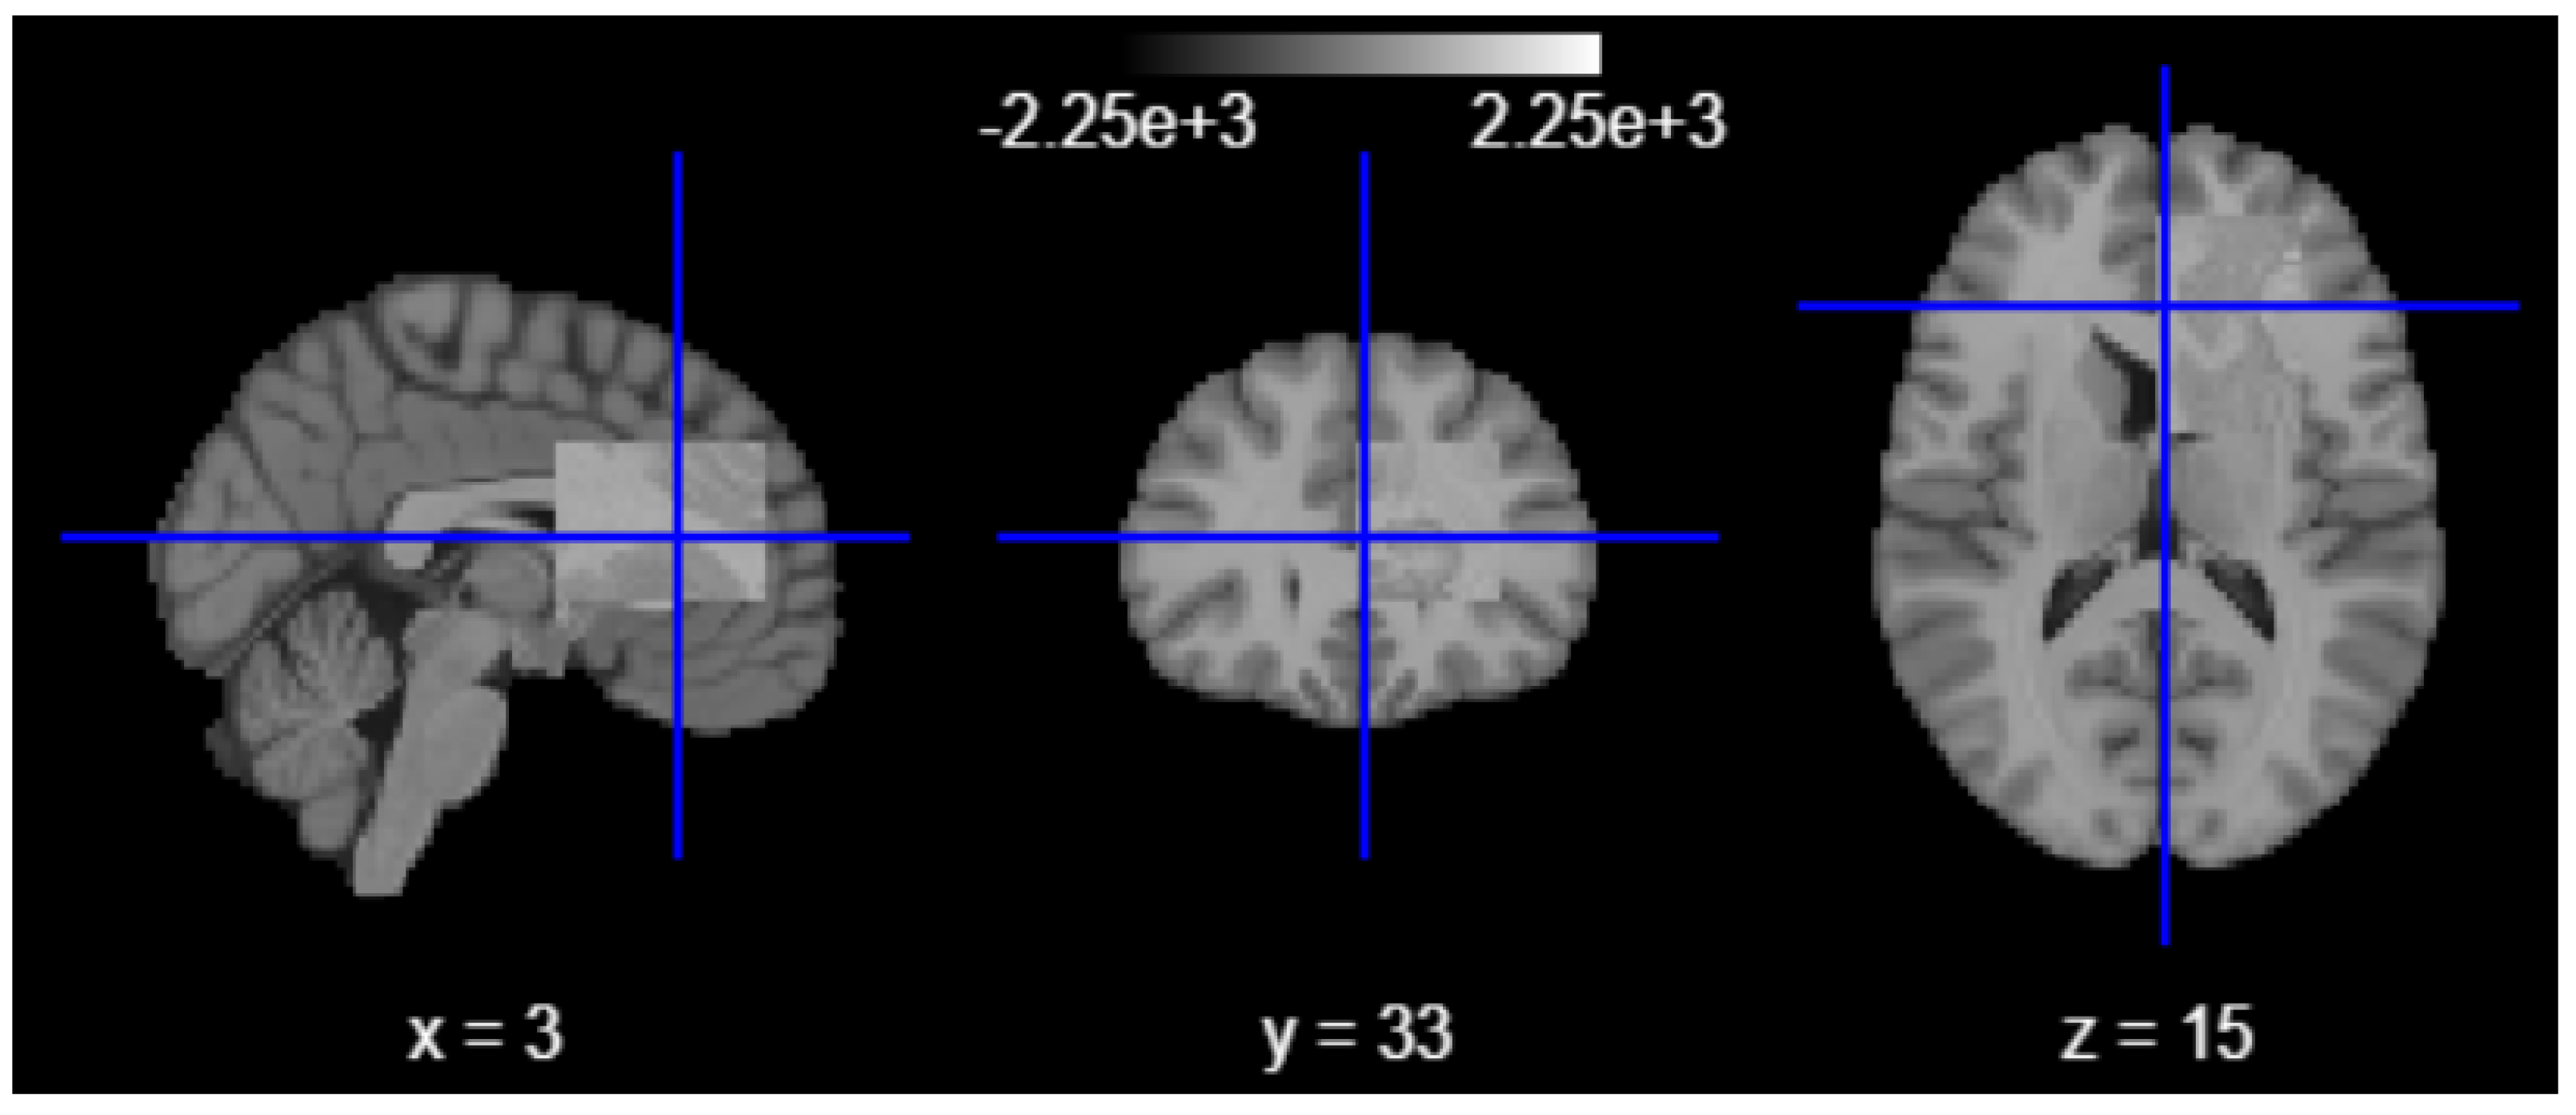

While quantitative metrics such as the Dice similarity coefficient provide essential numerical validation, the anatomical plausibility and spatial coherence of segmentation outputs must also be verified visually. To this end, overlay visualizations were generated by superimposing the predicted hippocampus masks onto the original T1-weighted MRI scans across axial, sagittal, and coronal planes. Figure 3 presents visual inspection confirmation that the model reliably captured the hippocampal contour, preserving the medial temporal morphology without significant over-segmentation or leakage into adjacent structures such as the amygdala or lateral ventricles [34]. These overlays also helped identify edge cases with partial coverage or morphological anomalies, enabling refined interpretation of volumetric outputs.

Figure 3.

Overlay visualization on axial, sagittal, and coronal planes.